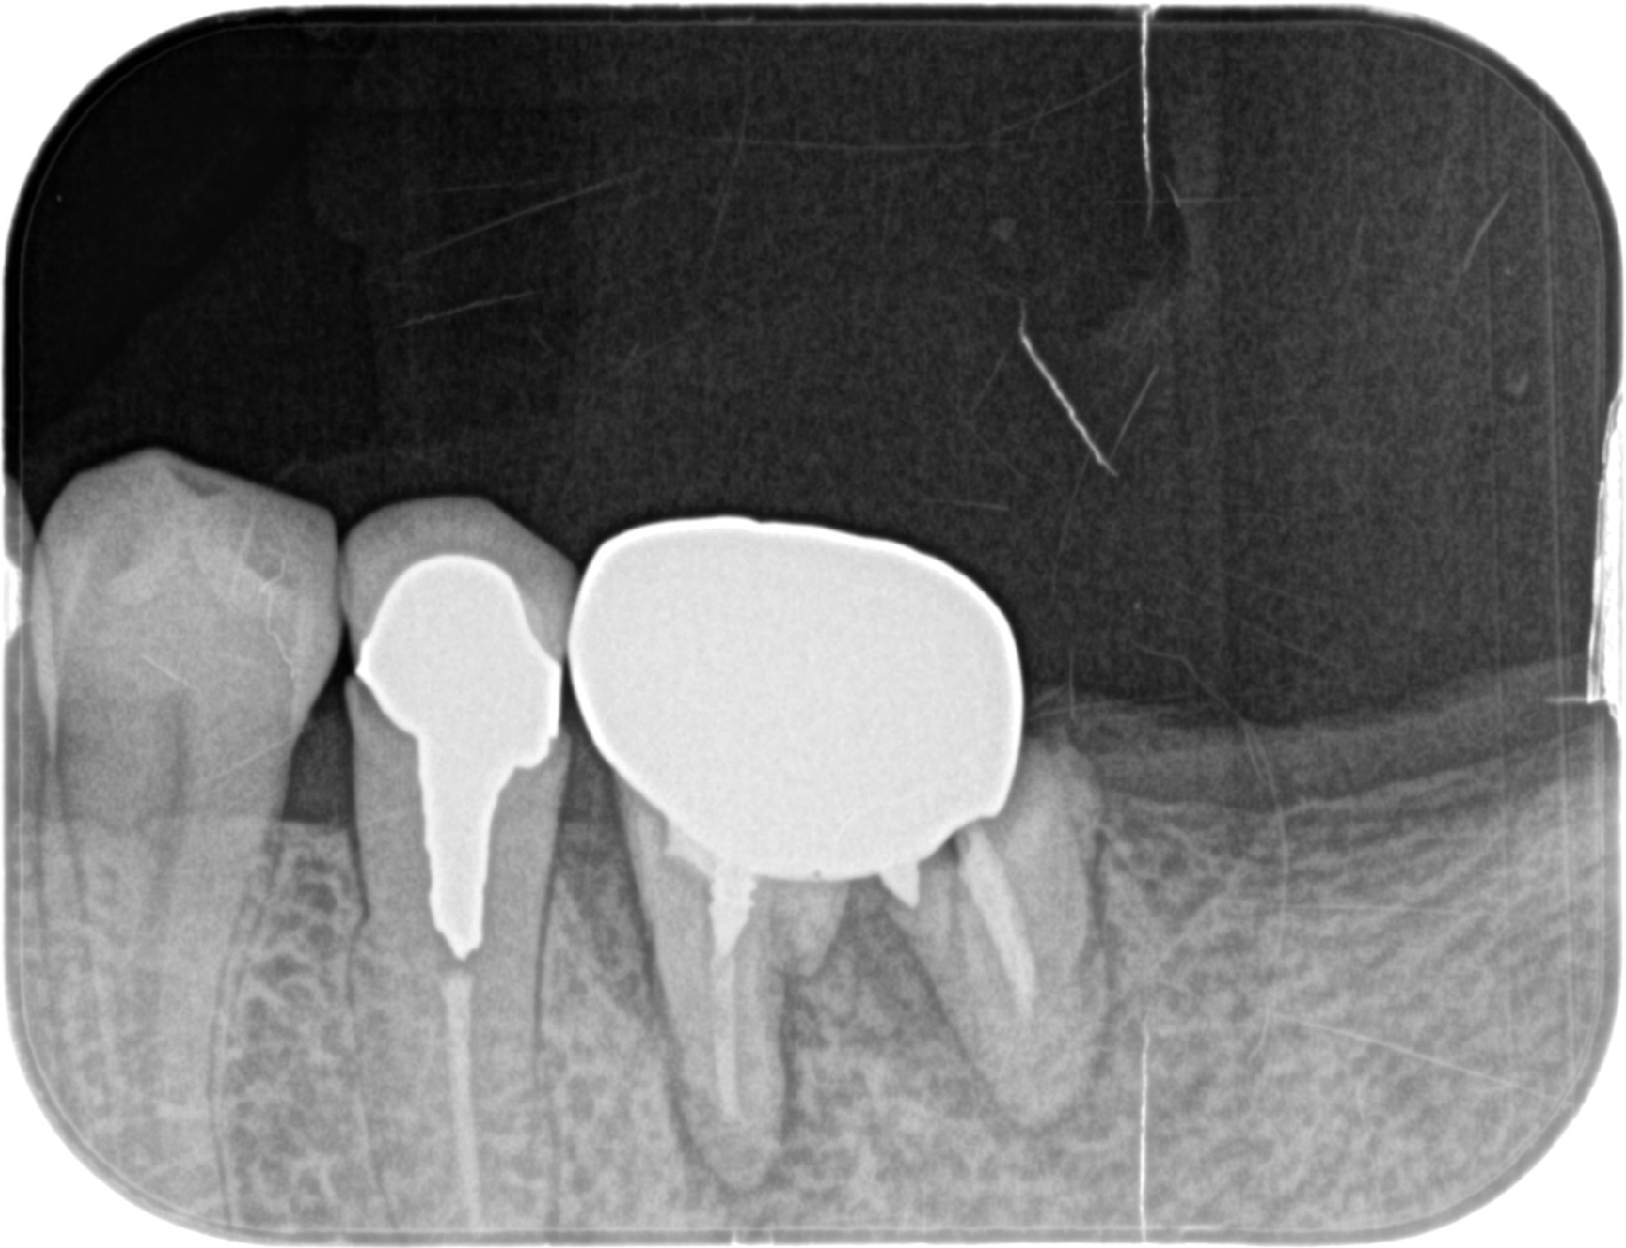

世界でも数多くの歯科医師に選ばれている「ストローマンインプラント」を採用。先進設備による精密な検査・診断と丁寧な処置で、埋入手術による痛みや腫れを減らし、安定性の高い長持ちするインプラント治療を提供しています。